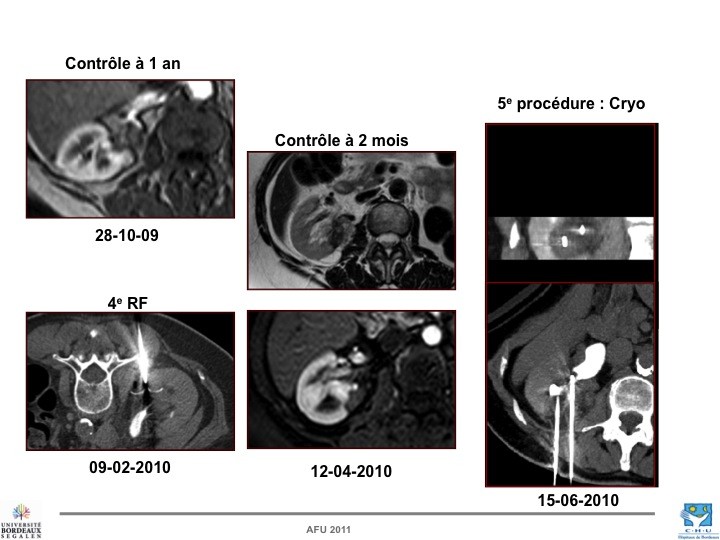

- Nos échecs

Nathalie RIOUX LECLERCQ (Rennes), Nicolas GRENIER (Bordeaux), Hervé BAUMERT (Paris)